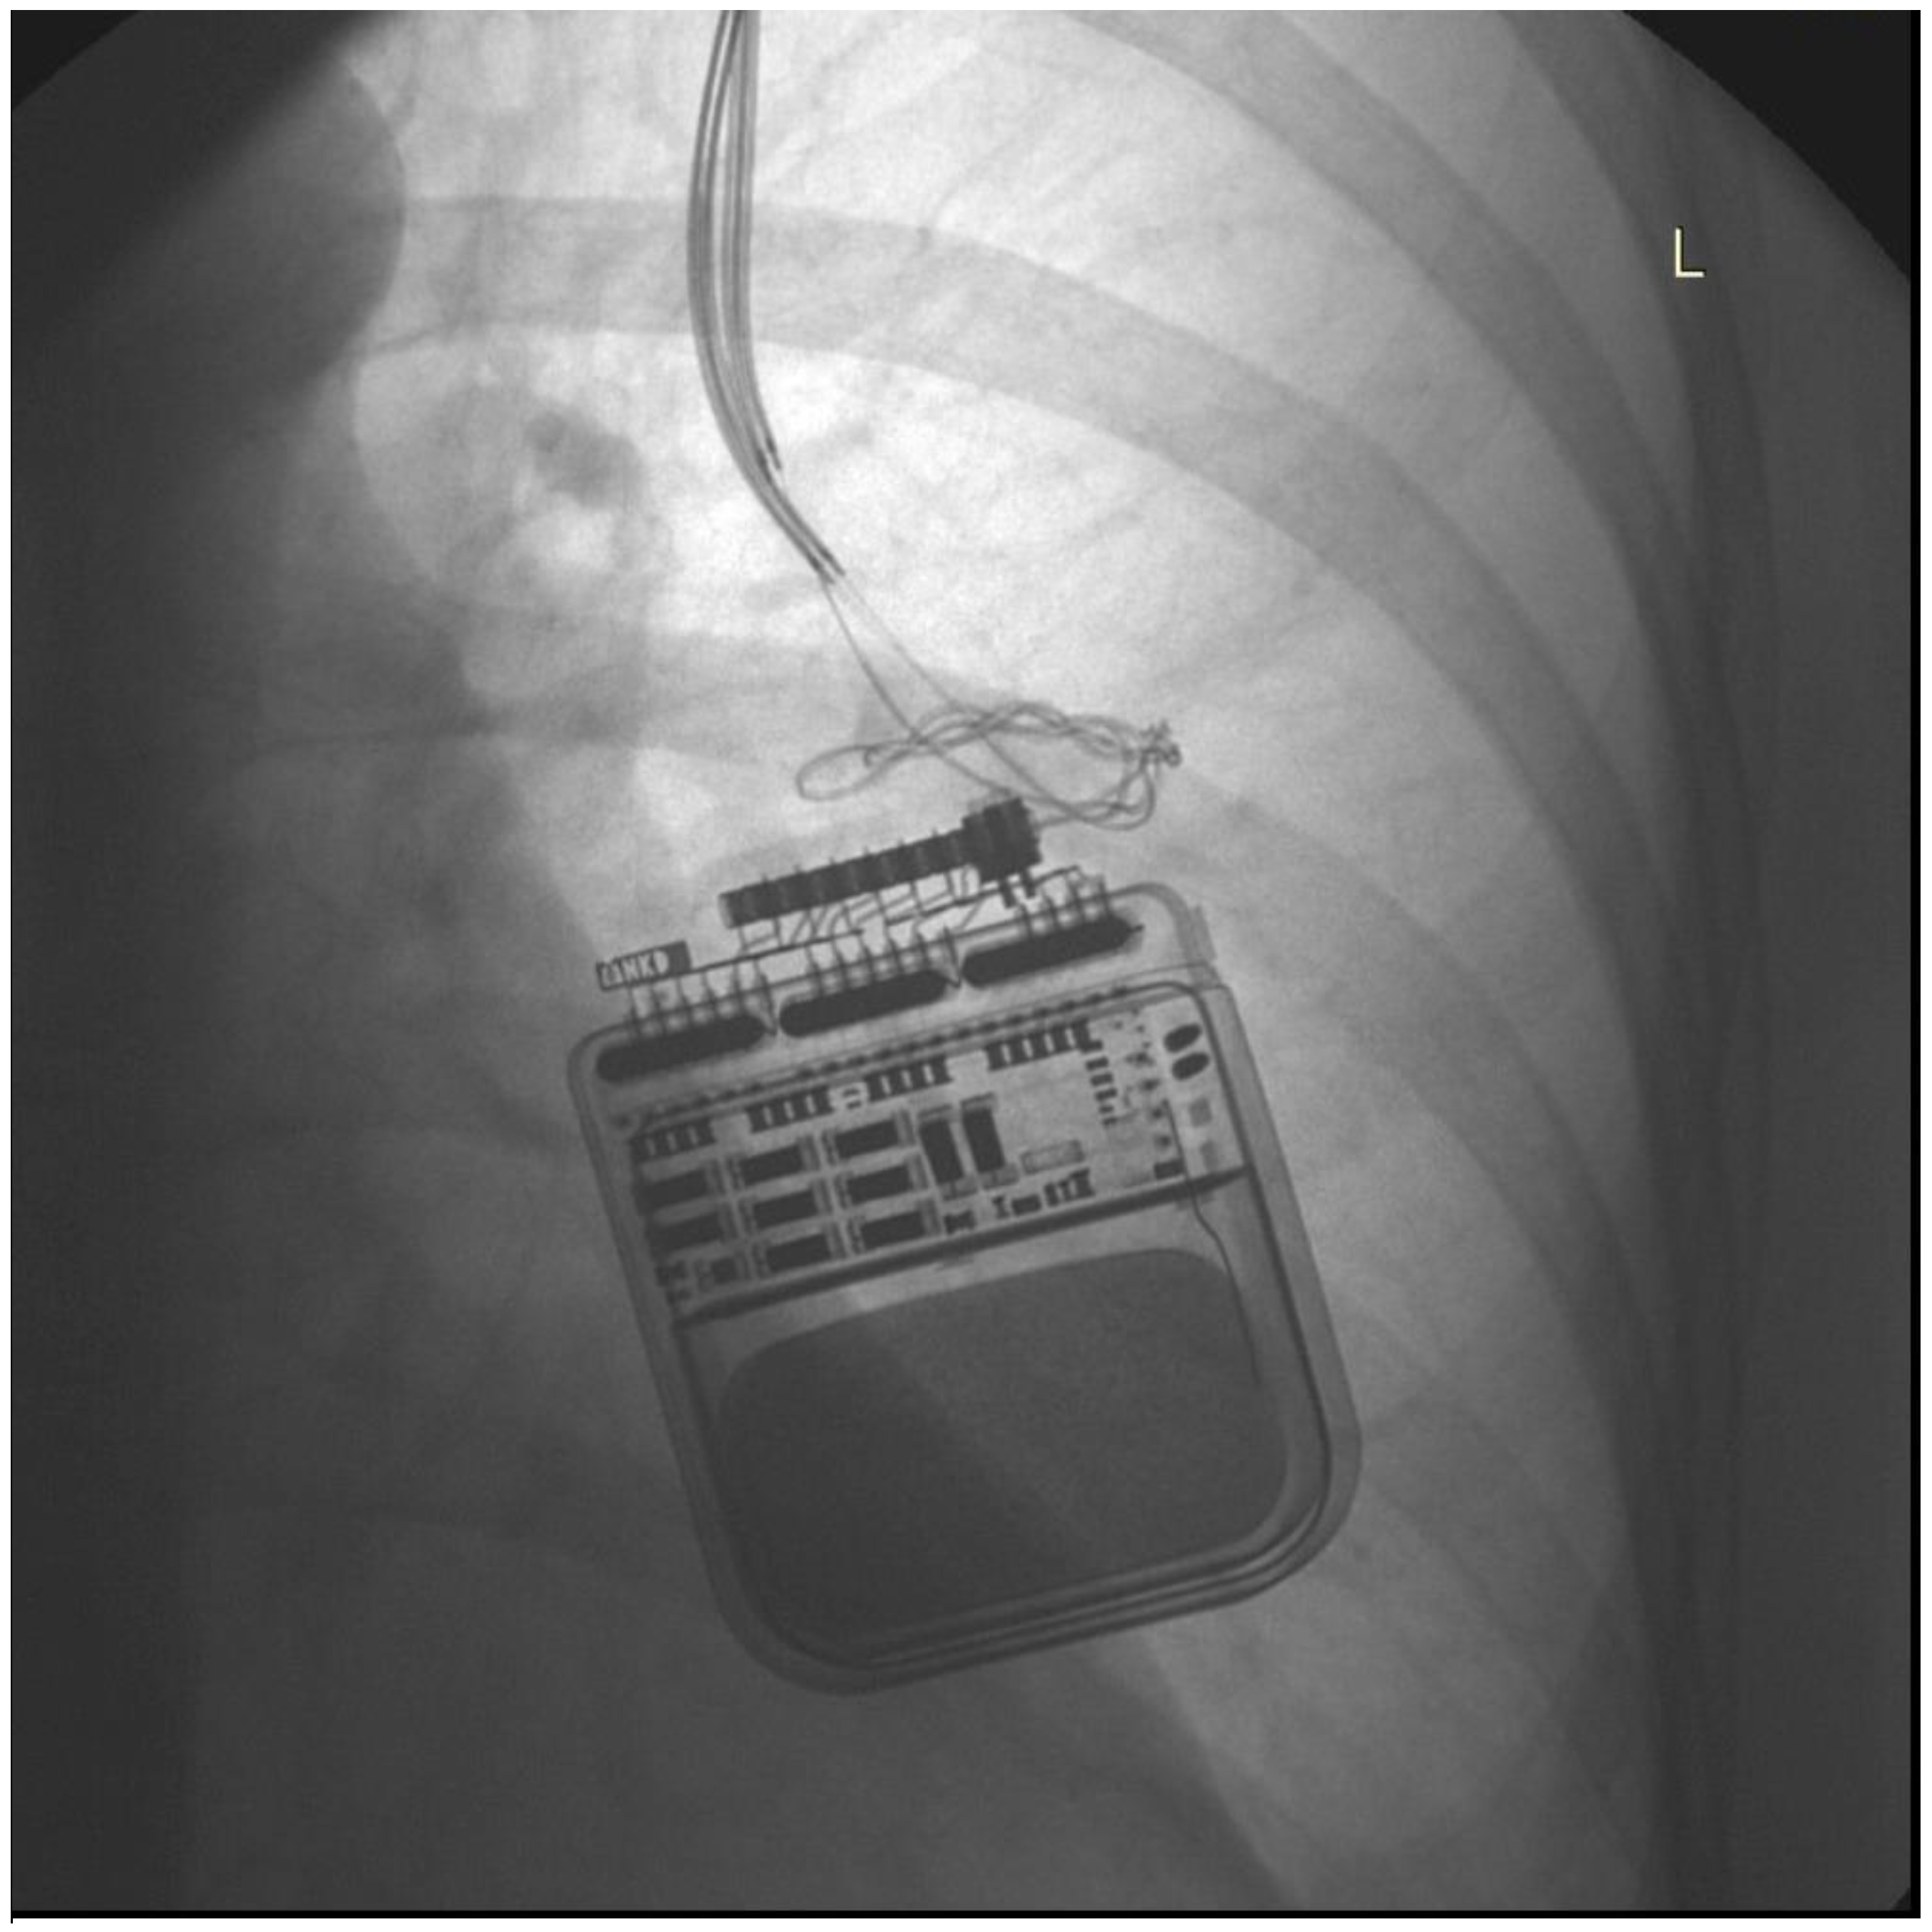

Illustrative case 1. Patient 11, is a 55-year-old female patient diagnosed with multifocal dystonia, manifesting as cervical and torsion dystonia, for the past 11 years. This patient achieved significant symptomatic improvement following bilateral GPi DBS and the implantation of a left dual-channel IPG (Activa PC), a treatment modality that has been effectively managing her condition for ten years. Battery replacements for the IPG were necessitated 5.5 years and again 3.5 years before the most recent procedure, due to the exhaustion of battery capacity. The patient was readmitted to the hospital, presenting with worsened uncontrolled muscle cramps and spasms, as well as difficulties in speaking and swallowing, symptoms suggestive of an intensification of her dystonia. Upon evaluation, impedance and current measurements for electrodes 0, 1, and 2 were within normal ranges, suggesting intact circuitry. However, electrode 3 displayed significantly elevated impedance levels (10,700–12,400) and diminished current output (0.6 mA), indicating a potential lead malfunction. Subsequent chest X-rays (Figure 1) revealed pronounced coiling of the DBS extension leads, a mechanical complication that could compromise DBS efficacy. An emergency surgical revision was necessitated. During the procedure, twisting of the DBS extension leads was observed, necessitating replacement. Additionally, the IPG was securely repositioned beneath the pectoralis fascia to mitigate future displacement and coiling risks. This intervention significantly improved the patient’s dystonic symptoms, with follow-up examinations revealing normalization of impedance levels.

Figure 1. Chest X-ray showing IPG and coiling of extension wires.